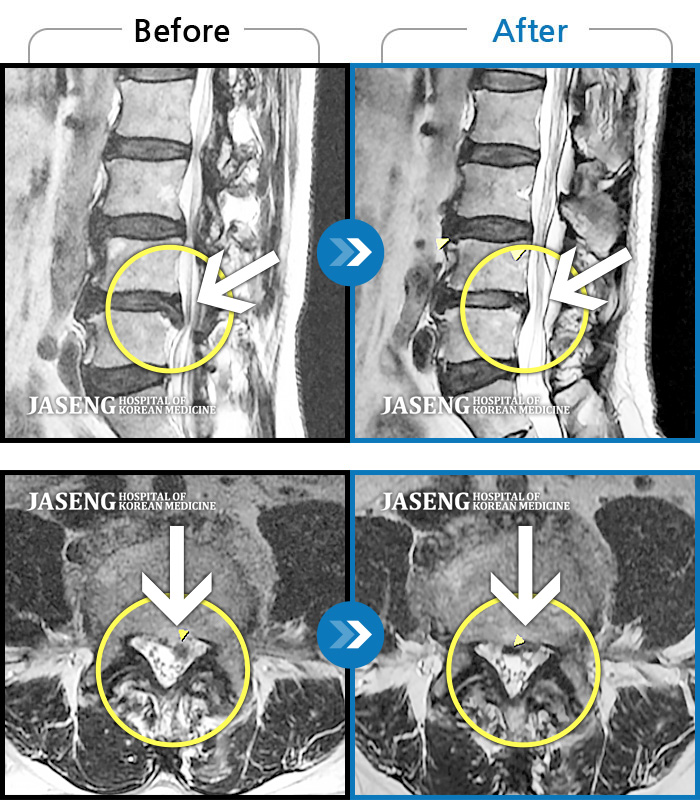

허리협착증으로 입원치료했는데 너무 친절하게 설명도 잘 하시고 치료도 잘 해주셔서 덕분에 오늘 퇴원합니다 원재균원장님 감사합니다~^^

아내가 무릎관절과 척추협착증세로 근 20여년 고생을~! 병원에선 수술권유에 걱정하든중, 수술않고 노후를 갈망하던중 오직 자생한방 병원의 신바로치료(일명 약침) 를 원재균 원장님께서 친가족처럼 친절과 따뜻한 치료를받고 있으며, 아내는 엄청호전으로 대만족 으로 노후를 잘 보낼수있게됐다고 원재균원장님께 감사의 마음을 전합니다. 남편으로서 정말 고맙고 감사합니다! 원재균원장님 !! 자생한방 신바로치료 선택을 정말한것 같습니다! 항시 가족처럼 치료를 잘 해주시는 원장님께 감사와 고마움을 드립니다 !! 원장님~!!!

평소 혈압으로 10년이상 등산, 헬스등 운동을 꾸준히 해오며 양측무릎과 허리통증이 심해 정형외과에서 무릎 퇴행성 관절염, 척추 협착증으로 진단 받았습니다 특히 계단 내려올때 내리막길 통증이 심하며 허리는 서있을경우 통증이 많이 올라옵니다 정형외과에서 수술권유해서 주변지인들로 수술 휴유증으로 약을 복용해도 통증이 잡히지않고 오히려 더 아픈 경우를 봐서 수술 않고 치료 할수 있는 병원을 찾다 지인 소개로 원재균 원장님을 뵙게 되었습니다 선한인상과 친절한 모습과 말투에서 우선 마음이 편안한 느낌 이었습니다 최대한 환자를 배려하는 행동이 몸에 배였다고 할까요 ㅎ 일반 정형외과나 병원에서는 볼수없는 모습에 깜짝 놀랄 정도 였습니다 정형외과에서 찍은 자료를 보시고 수술 안하고도 한방으로 약침, 침, 부항, 한약으로 치료받아 통증이 줄어들고, 일상생활이 가능할수 있다고 말씀 하셨습니다 관절이라 사용할수 있을때까지 사용하는게 좋다는게 저의 생각과 같았습니다 수술을 너무 싫어하는 저에겐 정말 도전해 볼만 했습니다 원장님을 믿고 치료한지 이제 한달이 다되어가는데 이제는 정형외과 약 안먹고도 극심한 통증없이 비오는 날만 한번씩 통증이 있는 정도 입니다 매번 내원시 그동안 어떻게 지내셨는지 통증이 어땠는지 세심하게 챙기시며 저를 살뜰히 봐주시는게 마음이 따뜻하게 느껴지고 치료받고 나면 좋아지는 느낌입니다 실력도 좋고, 마음도 따뜻한 원재균 원장님 감사의 표현을 꼭 하고싶었습니다" 진심으로 감사합니다 "